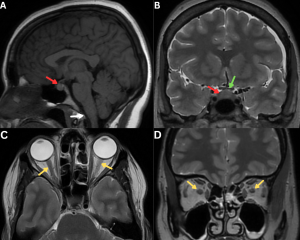

Fig 5: Figure A: Sagittal T1-weighted MRI demonstrates an enlarged pituitary gland (red arrow). Sagging of the brain is also evident, with inferior displacement of the brainstem and cerebellar tonsils (white arrow).

Figure B: Coronal T2-weighted MRI shows an enlarged pituitary gland (red arrow) extending into the suprasellar cistern and indenting the optic chiasm (green arrow).

Figures C and D. Axial and coronal T2-weighted MR images demonstrating collapsed bilateral optic nerve subarachnoid spaces (yellow arrows) secondary to low CSF pressure